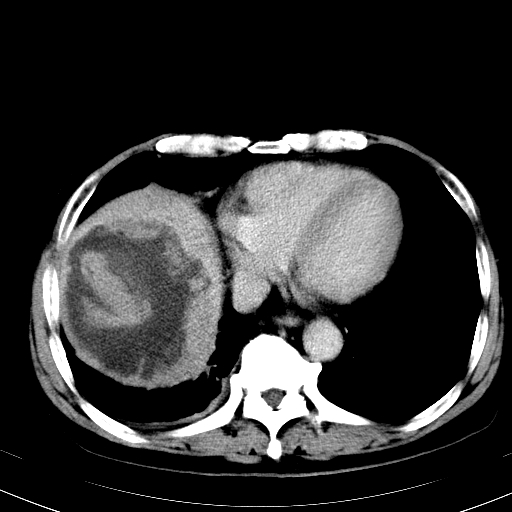

肝癌

肝癌很典型。

支持肝癌,查一下afp吧!

支持肝癌诊断。

考虑:肝癌。建议行mri检查。

支持肝癌。